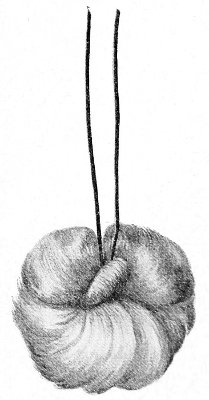

Suppuration of the vulvo-vaginal gland is accompanied by marked swelling and peripheral edema. The swelling may extend to the anus, and is of characteristic shape (Fig. 17). The pain is always severe. Fluctuation is first apparent on the inner surface of the labium majus. If the condition is not treated, one or more fistulous openings appear below the orifice of the duct, and the pus is discharged. The condition then becomes chronic. The fistulous openings persist. Acute inflammation disappears from the gland, leaving it in a condition of hypertrophic induration. A thin, milky or greenish, purulent fluid may be pressed out of the duct or the fistulous openings. Infection from this discharge may be communicated to man, or may ascend the genital 40 tract, producing inflammation of the endometrium or of the Fallopian tubes.

Fig. 17.—Abscess of right vulvo-vaginal gland.

In abscess of the vulvo-vaginal gland a free incision should immediately be made into the labium at the junction of the skin and the mucous membrane. The interior should be wiped out with pure carbolic acid and the cavity packed with gauze. If the disease is first seen in the chronic stage, after the abscess has evacuated itself, the only method of cure is to excise, with curved scissors, the whole of the indurated gland, the duct, and the fistulous tracts. The wound may be left open and packed, or it may be closed immediately with buried catgut sutures.